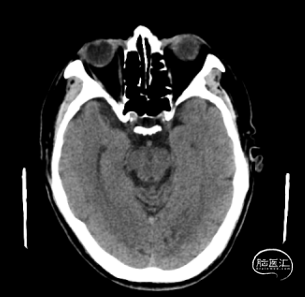

影像资料

排除出血。

术后CT,未见明显出血或梗死。